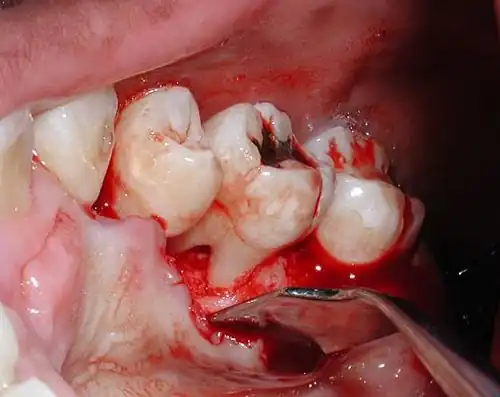

Evidence of furcal bone loss on #18 (lower left permanent second molar), along with a mesial vertical defect on the same tooth. The bent "stick" on the left of the tooth is a piece of gutta percha being used to trace the defect.